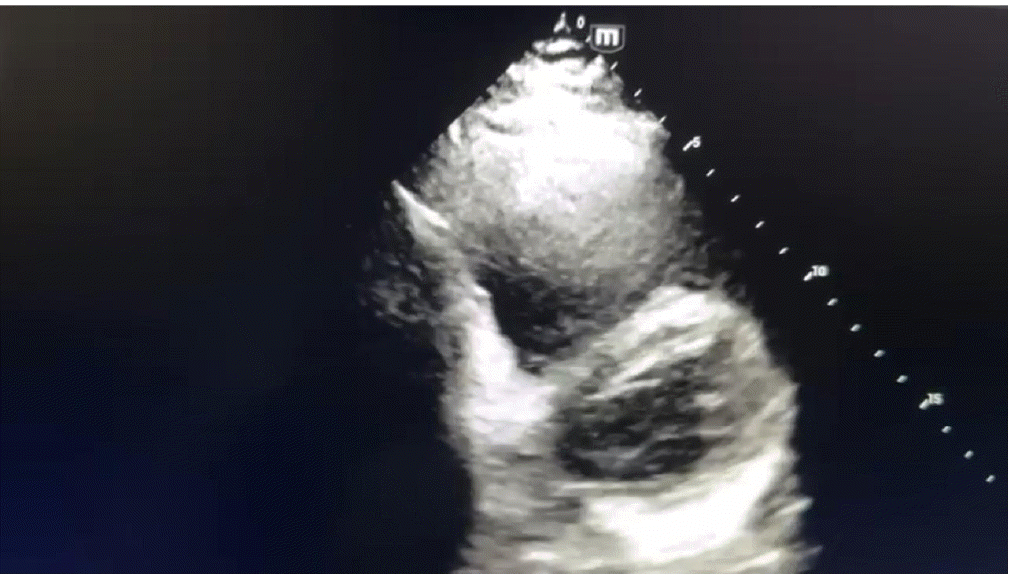

In view of severe respiratory distress and worsening hemodynamic status, he was intubated, and vasopressor commenced after fluid resuscitation. Computed tomography brain, chest and abdomen without contrast were done in view of high creatinine which revealed hemorrhagic brain contusion in the right posterior parietal and left higher parietal lobes. Two-dimensional echocardiography revealed severely dilated right atrium and right ventricle, jerky inter-ventricular septum with shift toward left ventricle, severe right ventricular dysfunction, and normal left ventricular systolic function (Figures 1-3). The lower extremity venous doppler showed evidence suggestive of thrombosis in bilateral superior femoral veins and left popliteal vein. Arterial blood gas analysis revealed nearly compensated metabolic acidosis with high lactate and hyperglycemia. On admission, lab include D-dimer of >20,000 ng/ml, serum creatinine 2.3 mg/dl, white blood cell counts 13,600 per microliter with normal hemoglobin and platelets counts, prothrombin time (PT) 23.1 seconds, international normalized ratio 1.7, and activated partial thromboplastin time (aPTT) 59.5 seconds. Liver function test revealed mildly elevated alanine transaminase and aspartate transferase (161 and 137 unit, respectively).